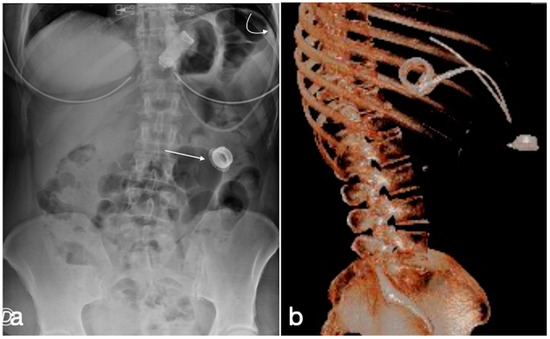

Figure 11. Gastric banding, detachment of the catheter from the port. A female patient in whom it was no longer possible to adjust the gastric banding. In the CT scout, the detachment of the catheter extremity (a, curved arrow) from the port (a, straight arrow) is clearly evident. In (b), the same findings are shown in the volume three-dimensional reconstruction.